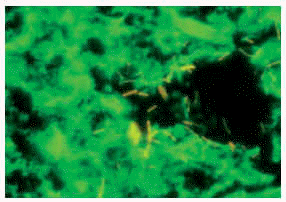

Es el método más sencillo, rápido y económico para el diagnóstico microbiológico, aunque presenta una sensibilidad muy inferior al cultivo (entre un 22-80 %), según donde se haya efectuado el estudio y del tipo de muestras estudiadas6. Las muestras respiratorias son las de mayor rentabilidad y siempre que se pueda se realizará concentración para incrementar la sensibilidad. En las técnicas de tinción utilizadas como la clásica de Ziehl-Neelsen o la de Kinyoun, aparecen de color rojo (fig. 1). La variante fluorocrómica (auramina) muestra los bacilos amarillo-naranja fluorescente, se visualizan más campos de la muestra al requerir objetivo de menor aumento (cribado más rápido y exhaustivo) y es la preferida por los microbiólogos (fig. 2); además, en los casos dudosos puede realizarse una tinción de Ziehl-Neelsen en el mismo portaobjetos.

Fig. 1.--Tinción de Ziehl-Neelsen.

Fig. 2.--Tinción de auramina con bacilos amarillo-naranja fluorescentes.